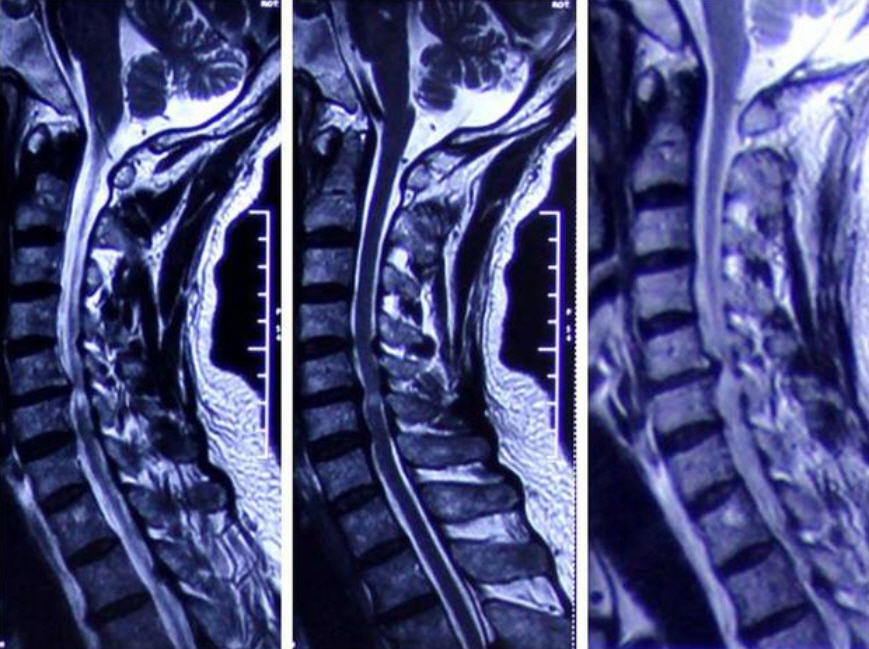

彭宝淦说,脊椎病可以从以下几个方面确诊:1.脊椎椎间盘退变或椎间肘部退变;2.病理改变累及周围组织;3.出现相应的临床病症和体征;4.有相应的影像学改变。

现在,对脊椎病的分类主要包括:颈型、神经根型、脊髓型和其他型。其中颈型脊椎病最多见,脑干型脊椎病最严重。“颈型脊椎病病人常常有枕部、颈部、肩部麻木等异常发觉,可伴有相应的胸痛点,影像学检测即显示为脊椎退行性改变。”彭宝淦说,“最严重的当属脑干型,会形成颈脑干的受压变性,进展到一定程度会造成手臂以下的完全性或不完全性的失明,上手臂活动障碍,即便出现,对病人本人、家庭和社会都将形成很大影响,并且或许是灾难性的。因此出现脊椎病初期病症要及早诊治,尽量避开这些状况的发生。”

在这些人的复查报告中,腰部影像一项都显示为“颈椎生理弯度消失变直”。但腰部弯度的改变会对健康导致这些影响,你们并不了解。“各种影像学征象对于脊椎病的确诊具备重要参考价值,但仅有影像学检测所见的脊椎退行性改变而无脊椎病临床病症者,不应确诊为脊椎病。”彭宝淦觉得,具备典型脊椎病临床表现,而影像学所见正常者,应留意排除其他疾病。

对于早已患上脊椎病的人,彭宝淦给出如下建议:第一,影像学检测是必不可少的,例如X光片、CT、核磁等,必要时还须要肌电图检测;第二,治疗脊椎病是个复杂的、需要多学科协作的过程,因此一定要去正规的专业诊所,不要迷信小医院的虚假宣传;第三,头部推拿和推拿要谨慎,当年出现过刮痧后外伤和推拿后失明的病例;第四,放疗是最后的选择,即便是急性的脑震荡骨折、椎间盘急性突出、脊髓外伤等特殊状况,通常应从非放疗医治开始,如无效果,再考虑放疗医治;第五,作为防治,养成良好的日常工作、生活习惯特别重要,少做低头族,多做髋部舒展锻练,提高体质,劳逸结合,会对脊柱起到挺好的保护作用。

手法推拿不仅仅推拿胸肌使之下垂,还包括了滑膜复位等“重手法”,所以不能随意按。在接受手法刮痧前,先要做CT、MRI等相关检测,看清楚脊椎病的类别。在脊椎病的类别中,血管根型、部分椎动脉型和交感型脊椎病,手法理疗疗效好,是适应证范围。